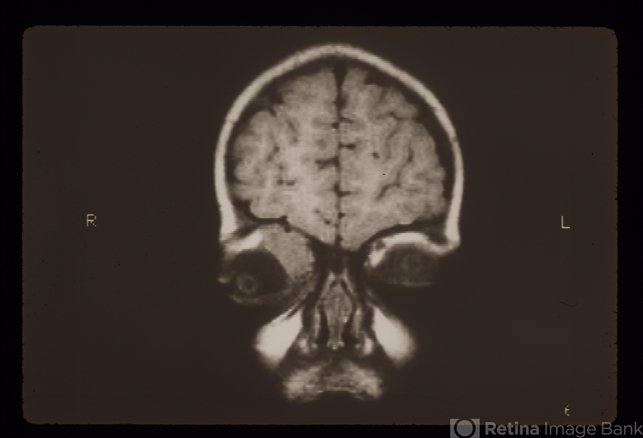

- Rhabdomyosarcoma R Orbit

- Condition/keywords

- rhabdomyosarcoma

- Four year old patient. CMC patient; embryonal rhabdo; CT, MRI, Clinical, and histology photos.